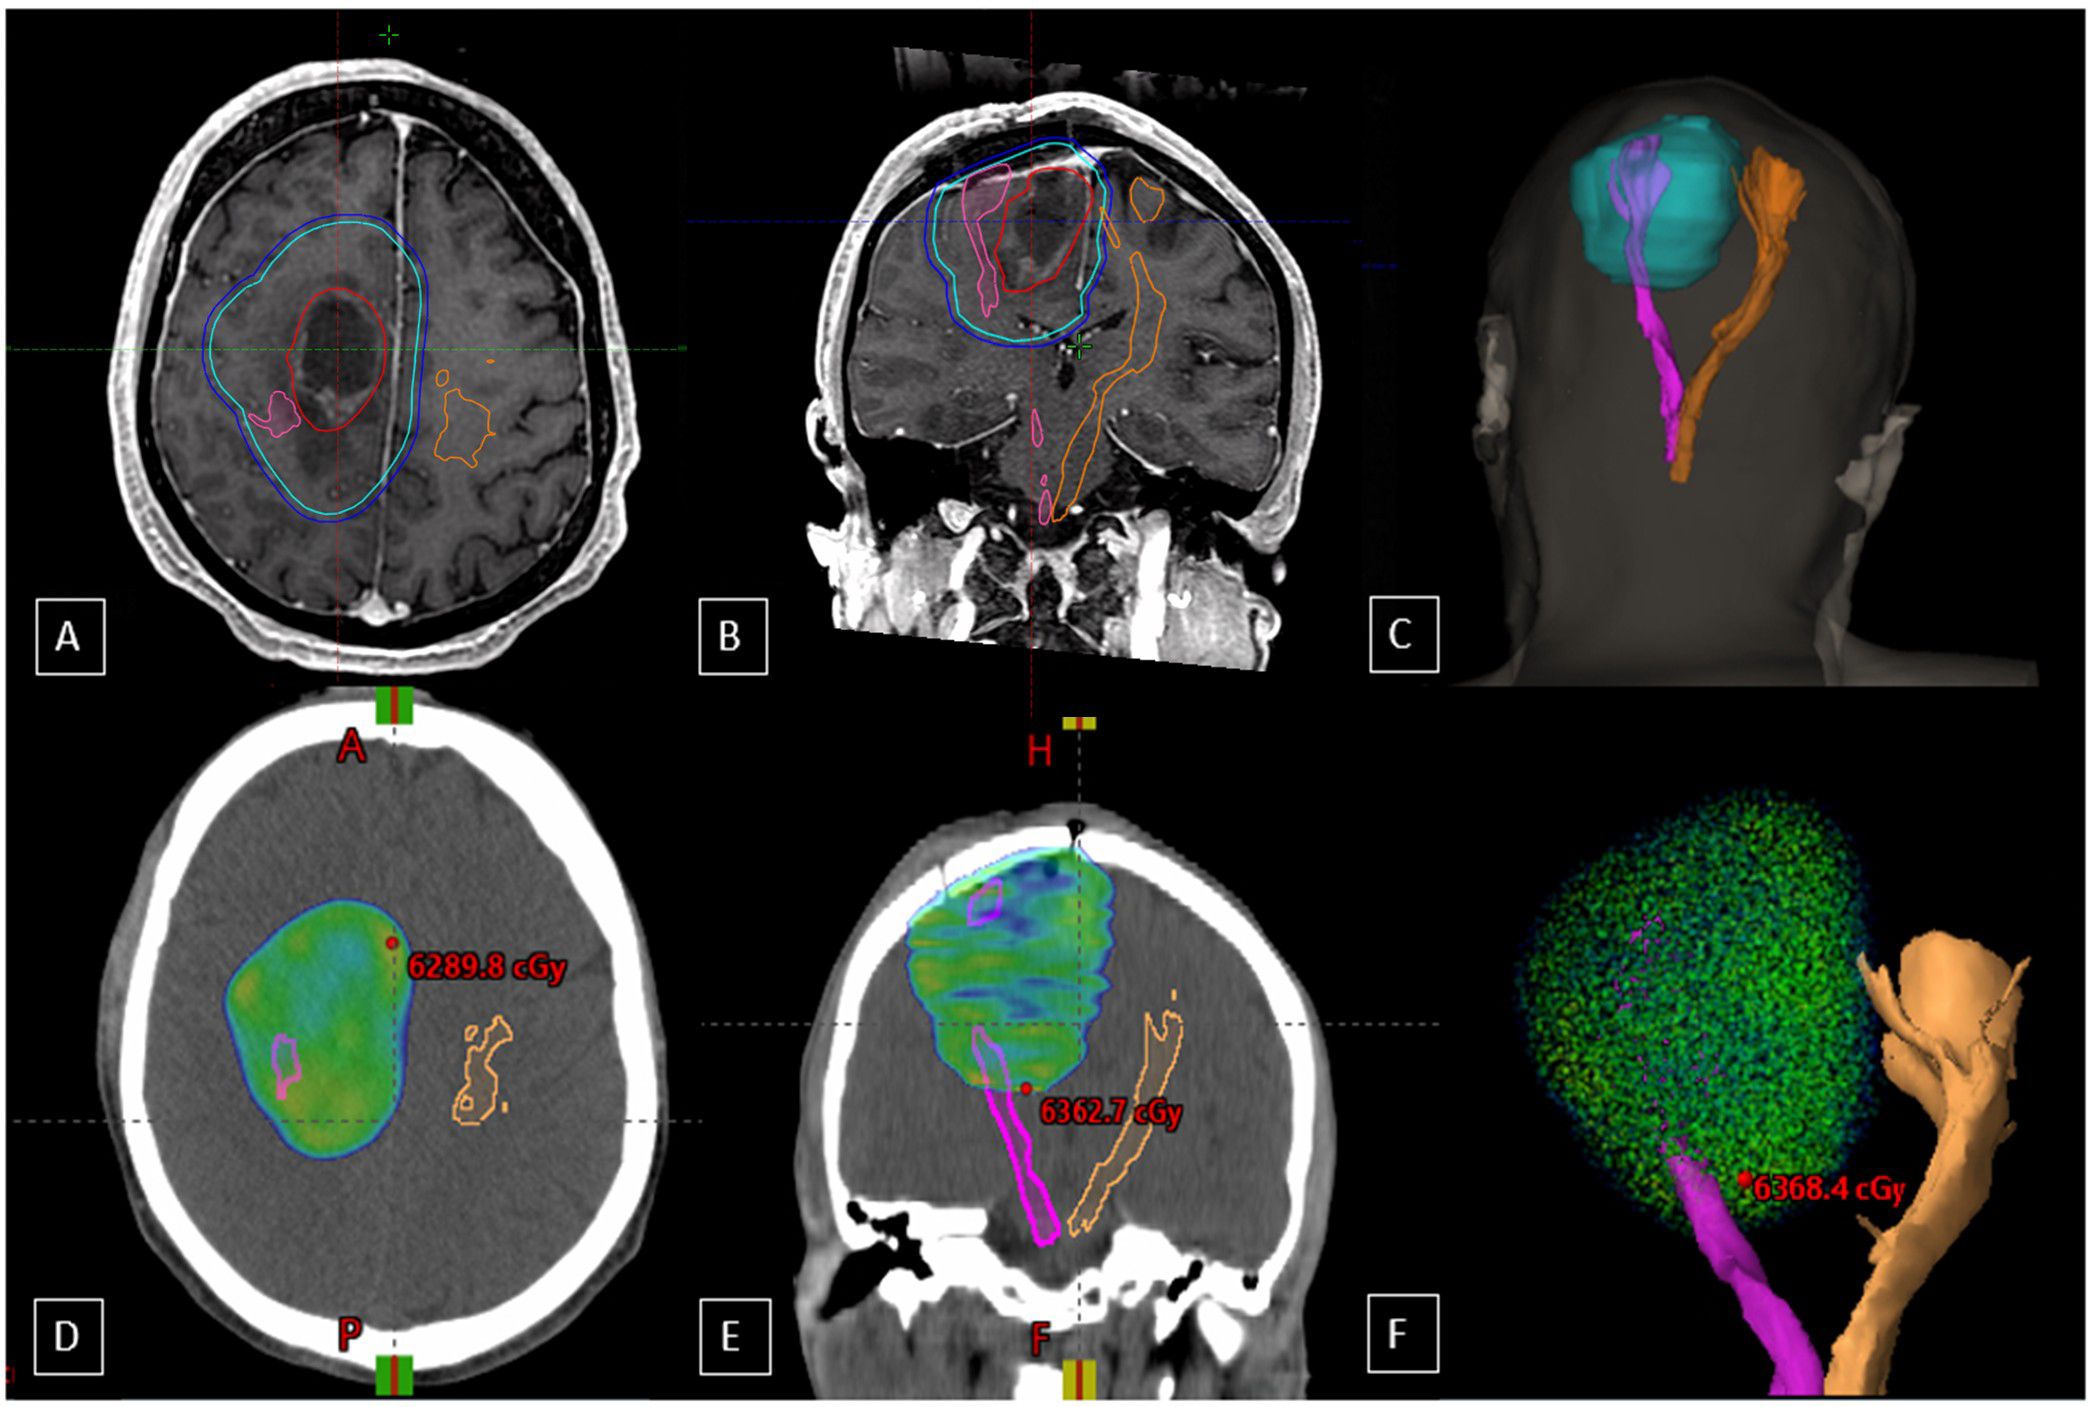

Introduction Wallerian Degeneration of the Corticospinal Tract (WDCT) is a scarcely reported complication of multimodal treatment for high-grade gliomas, which, despite its potential clinical impact, may lead to severe motor dysfunction and impair quality of life. Methodology This retrospective case series describes 13 adult patients with high-grade gliomas treated between 2018 and 2023 who developed imaging findings consistent with WDCT after receiving multimodal treatment. Clinical and radiological data were collected from medical records; a standardized imaging follow-up or functional scoring system was not applied. Tractography was retrospectively available for two cases, enabling its incorporation into radiotherapy planning system for CST precise delineation and corresponding dose estimation. Results WDCT was identified in 13 out of 192 high-grade glioma patients (6.8%). Diagnosis was based on T2/FLAIR hyperintensity along the ipsilateral CST with compatible clinical symptoms. Three cases developed WDCT after reirradiation, and seven (53.8%) had received bevacizumab prior to diagnosis: two during disease progression, two for the treatment of radionecrosis, and three as prophylaxis. Clinical symptomatology was detailed to 11 patients, 72.7% presented with hemiparesis, and 36.4% had seizures. In two cases, retrospective dose-volume analysis revealed CST mean doses ranging from 25.81 Gy to 42.83 Gy. Conclusions This retrospective series highlights WDCT as a potentially underrecognized complication in glioma patients undergoing multimodal treatment. While etiology is likely multifactorial, radiotherapy may play a contributing role. CST delineation, when tractography is available, may support individualized treatment planning, enable better assessment of dose exposure, and help identify patients at higher risk of motor decline. Further prospective studies are warranted to define dose thresholds and assess functional outcomes.